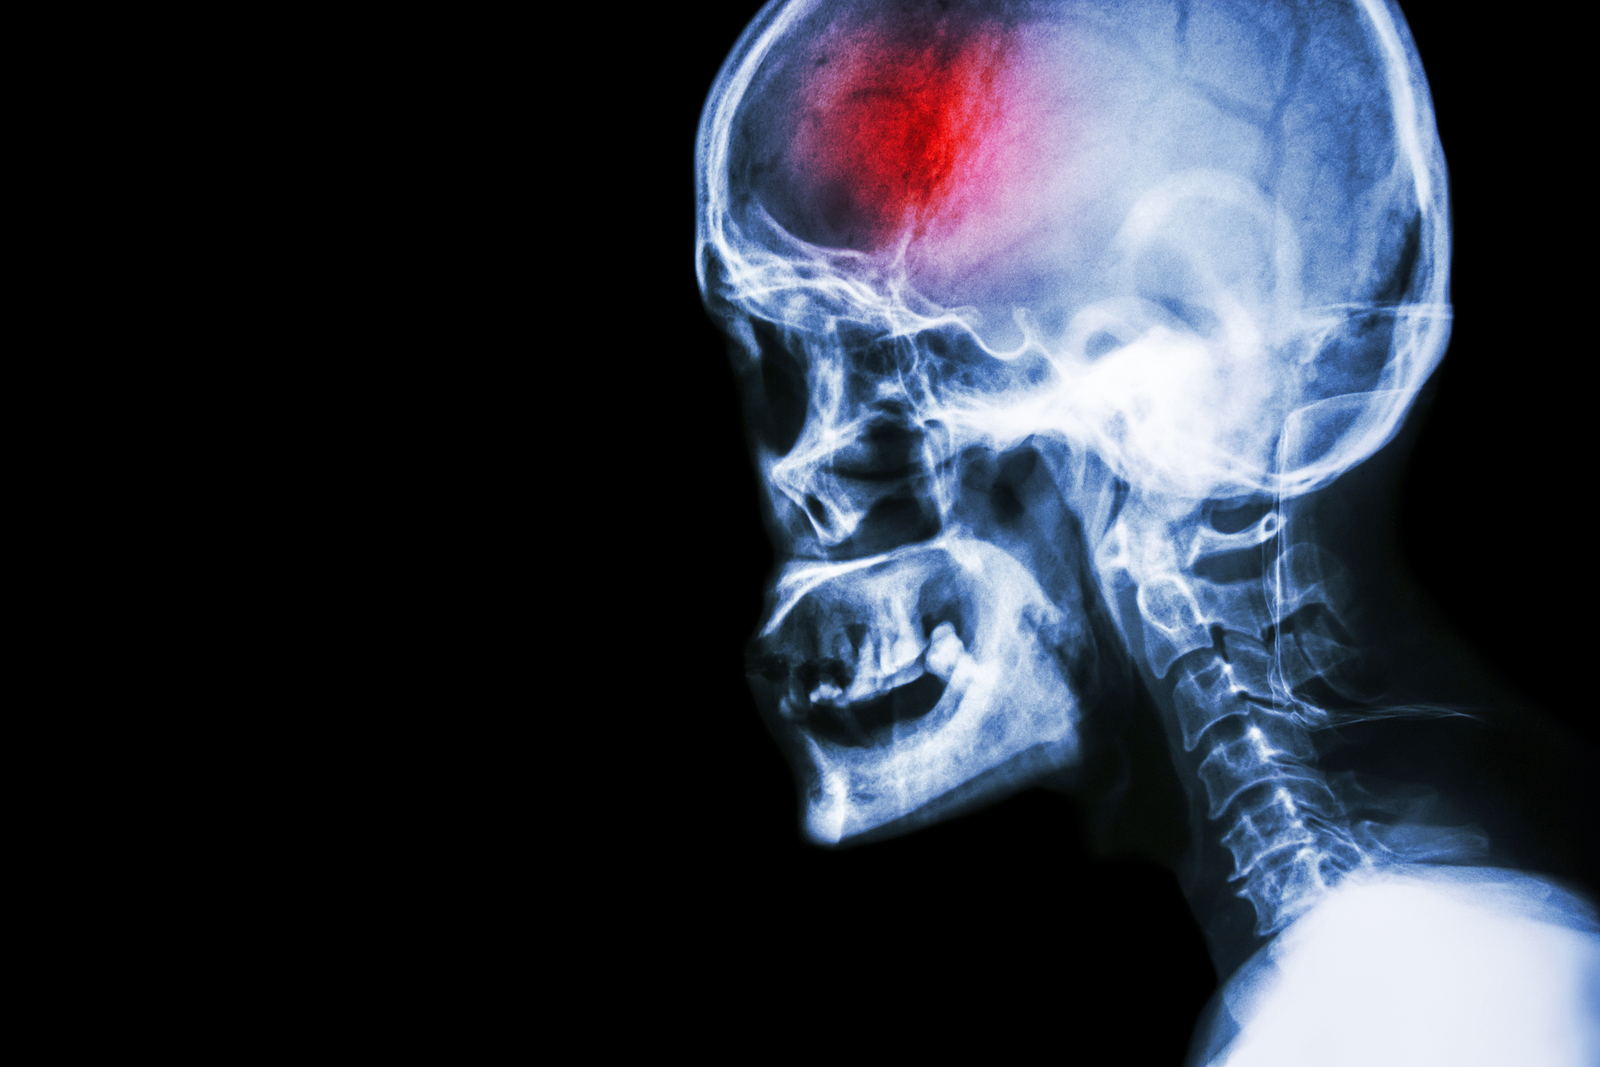

Diagnosis

The classic signs and symptoms of a stroke often create an obvious suspicion of stroke, however once at a medical centre, other objective tests are completed to confirm the stroke diagnosis. It is important for the medical team to determine which kind of stroke is occurring in order to assist with the most effective type of treatment.

Computed Tomography (CT) scan and/or Magnetic Resonance Imaging (MRI) scan: These tests are done on your brain and used to locate the exact location of the stroke and to determine if it has been caused by a blockage or a bleed. These tests can also help rule out other conditions that may be causing symptoms, such as an infection or a brain tumour

Several other tests may be conducted to assist in diagnosing a stroke, such as echocardiograms to look at the heart, or ultrasounds to check for the state of the carotid arteries in your neck.